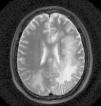

Se efectuó resonancia magnética por imágenes (RMI) con contraste en la que se observó extensa lesión subcortical en lóbulo frontal, parietal y occipital izquierdos, con extensión al esplenio del cuerpo calloso y mesencéfalo superior del lado izquierdo, y compromiso de los lóbulos parietal y occipital derechos. Las imágenes predominaban en lóbulos posteriores y dibujaban las fibras subcorticales en «U». No hubo realce con el contraste IV, ni efecto de masa sobre estructuras adyacentes de la línea media (figs. 1-5).

El VJC se reactiva ante cuadros de inmunosupresión grave, e induce la infección lítica de los oligodendrocitos con lesiones multifocales de desmielinización. La enfermedad tiene una prevalencia del 1 al 4% entre los pacientes con sida. El curso clínico es progresivo y con déficit neurológico focal en el 80% de los pacientes afectados. El examen del LCR es normal o con alteraciones inespecíficas, (hiperproteinorraquia moderada y pleocitorraquia mononuclear)4. La RM muestra la presencia de lesiones, por lo general bilaterales, simétricas o asimétricas, con predominio en lóbulos parieto-occipitales, bien delimitadas y localizadas en áreas periventriculares y en la sustancia blanca subcortical. Pueden ser únicas o múltiples, no refuerzan con el contraste, no están rodeadas de edema, ni producen efecto de masa, y dibujan las fibras subcorticales en «U» o fibras arcuatas; un tercio de los pacientes tienen compromiso de la fosa posterior. Entre un 5-10% de los casos, esta última localización se revela como la única manifestación de la enfermedad4. El diagnóstico se confirma por la PCR en el LCR. La sensibilidad de la prueba es variable (40-80%), posee una alta especificidad (mayor del 90%) y un valor predictivo positivo del 100%5.